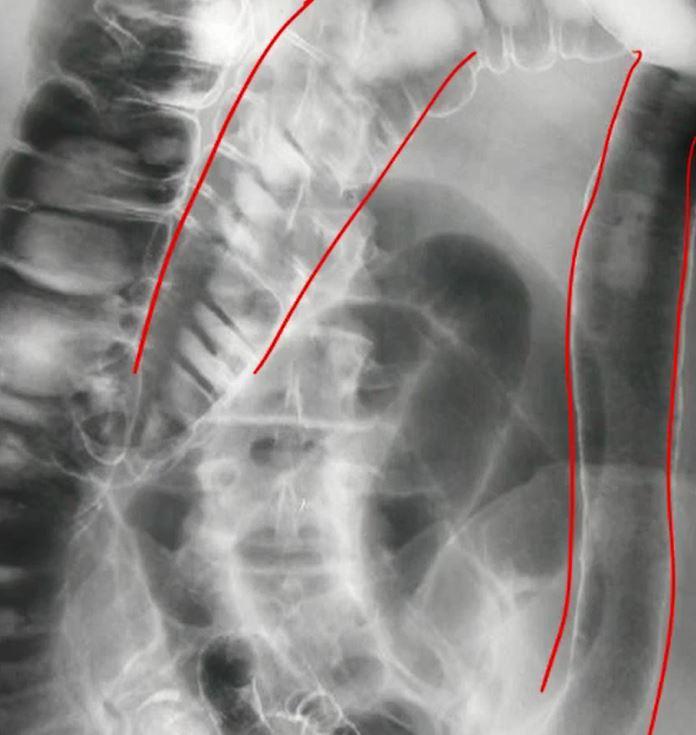

card image

duodenal atresia